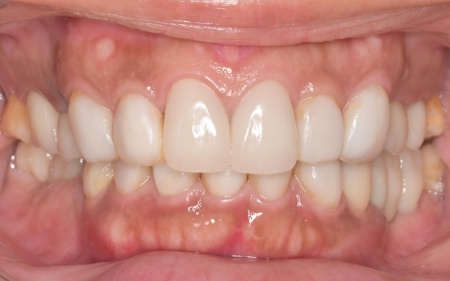

40代女性 乱れた歯並びと不安定な噛み合わせを矯正治療と被せ物で改善した症例

- 矯正歯科

- ワイヤー矯正

- 詰め物・被せもの

- セラミック・ジルコニア

- 抜歯

- ダイレクトボンディング

- 治療期間の目安 4年

- 治療回数の目安 45~50回

-

治療費総額の目安

約2,370,000円

(矯正治療、ジルコニアクラウン、ダイレクトクラウン)

治療のリスク

・外科処置後に痛みが長引く場合があります。必要に応じ痛み止めを併用します ・治療中、装置によってまれに頬の内側が傷つき、口内炎になる場合があります ・歯の移動に伴って、違和感や痛みを感じる場合があります ・正しいブラッシングやメンテナンスを行わない場合、虫歯や歯周病のリスクが高まります ・装...

by.鈴木歯科医院